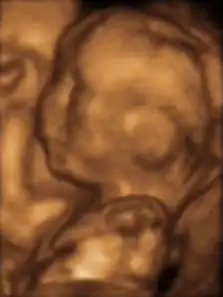

A dating scan at 12 weeks

Obstetric ultrasonography is routinely used for dating the gestational age of a pregnancy from the size of the fetus, determine the number of fetuses and placentae, evaluate for an ectopic pregnancy and first trimester bleeding, the most accurate dating being in first trimester before the growth of the foetus has been significantly influenced by other factors.[22] Ultrasound is also used for detecting congenital anomalies (or other foetal anomalies) and determining the biophysical profiles (BPP), which are generally easier to detect in the second trimester when the foetal structures are larger and more developed.[23]

X-rays and computerized tomography (CT) are not used, especially in the first trimester, due to the ionizing radiation, which has teratogenic effects on the foetus.[24] No effects of magnetic resonance imaging (MRI) on the foetus have been demonstrated,[25] but this technique is too expensive for routine observation. Instead, obstetric ultrasonography is the imaging method of choice in the first trimester and throughout the pregnancy, because it emits no radiation, is portable, and allows for realtime imaging.[26]

The safety of frequent ultrasound scanning has not been confirmed. Despite this, increasing numbers of women are choosing to have additional scans for no medical purpose, such as gender scans, 3D and 4D scans.[27] A normal gestation would reveal a gestational sac, yolk sac, and fetal pole.[28]

The gestational age can be assessed by evaluating the mean gestational sac diameter (MGD) before week 6, and the crown-rump length after week 6. Multiple gestation is evaluated by the number of placentae and amniotic sacs present.[29]